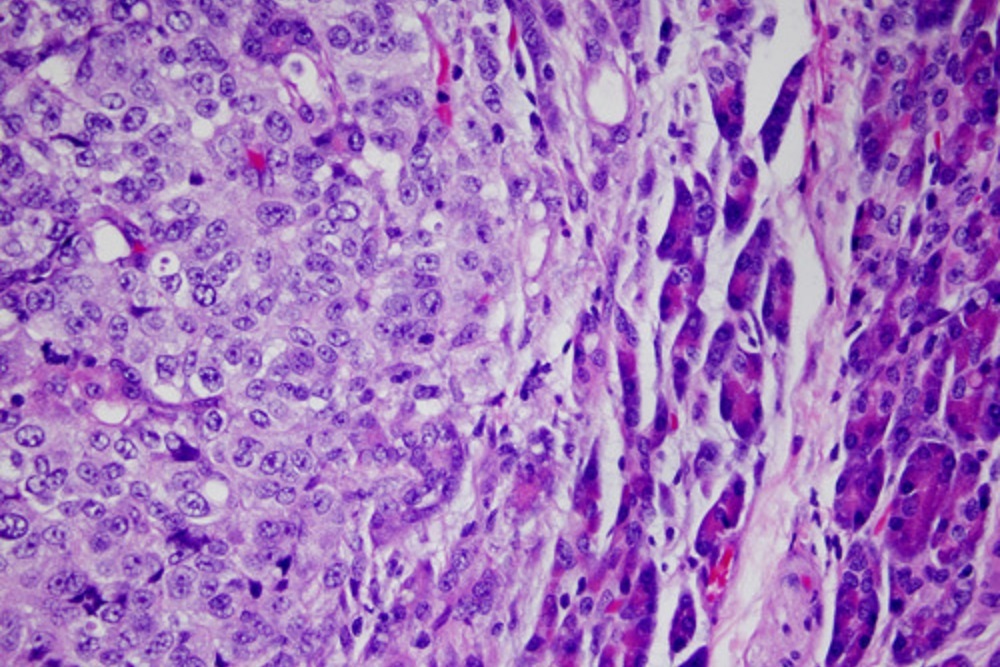

Amgen's Phase 2 study evaluating Imlygic combined with Yervoy as a treatment for patients with unresectable Stage IIIB-IV met its primary endpoint.

In the study, the combination of Imlygic with the immune checkpoint inhibitor Yervoy proved to be more effective than the use of Yervoy on its own. The combination more than doubled objective response rate (ORR), defined as the proportion of patients with tumor size reduction, in patients with unresectable Stage IIIB-IV melanoma. Amgen presented these results at the 53rd Annual Meeting of the American Society of Clinical Oncology.